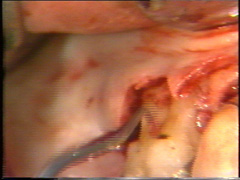

Visión palatina:

Eliminación del tejido de granulación.

En la superficie

palatina del central, hay un defecto grande en la superficie de la raíz. Probablemente

sea una fractura que ocurrió en relación con el accidente. El tejido de

granulación se ha formado en el defecto que se limpia completamente. Postoperatoriamente es necesario poner

apicalmente el colgajo en relación con el defecto de la raíz para crear una condición higiénica manejable